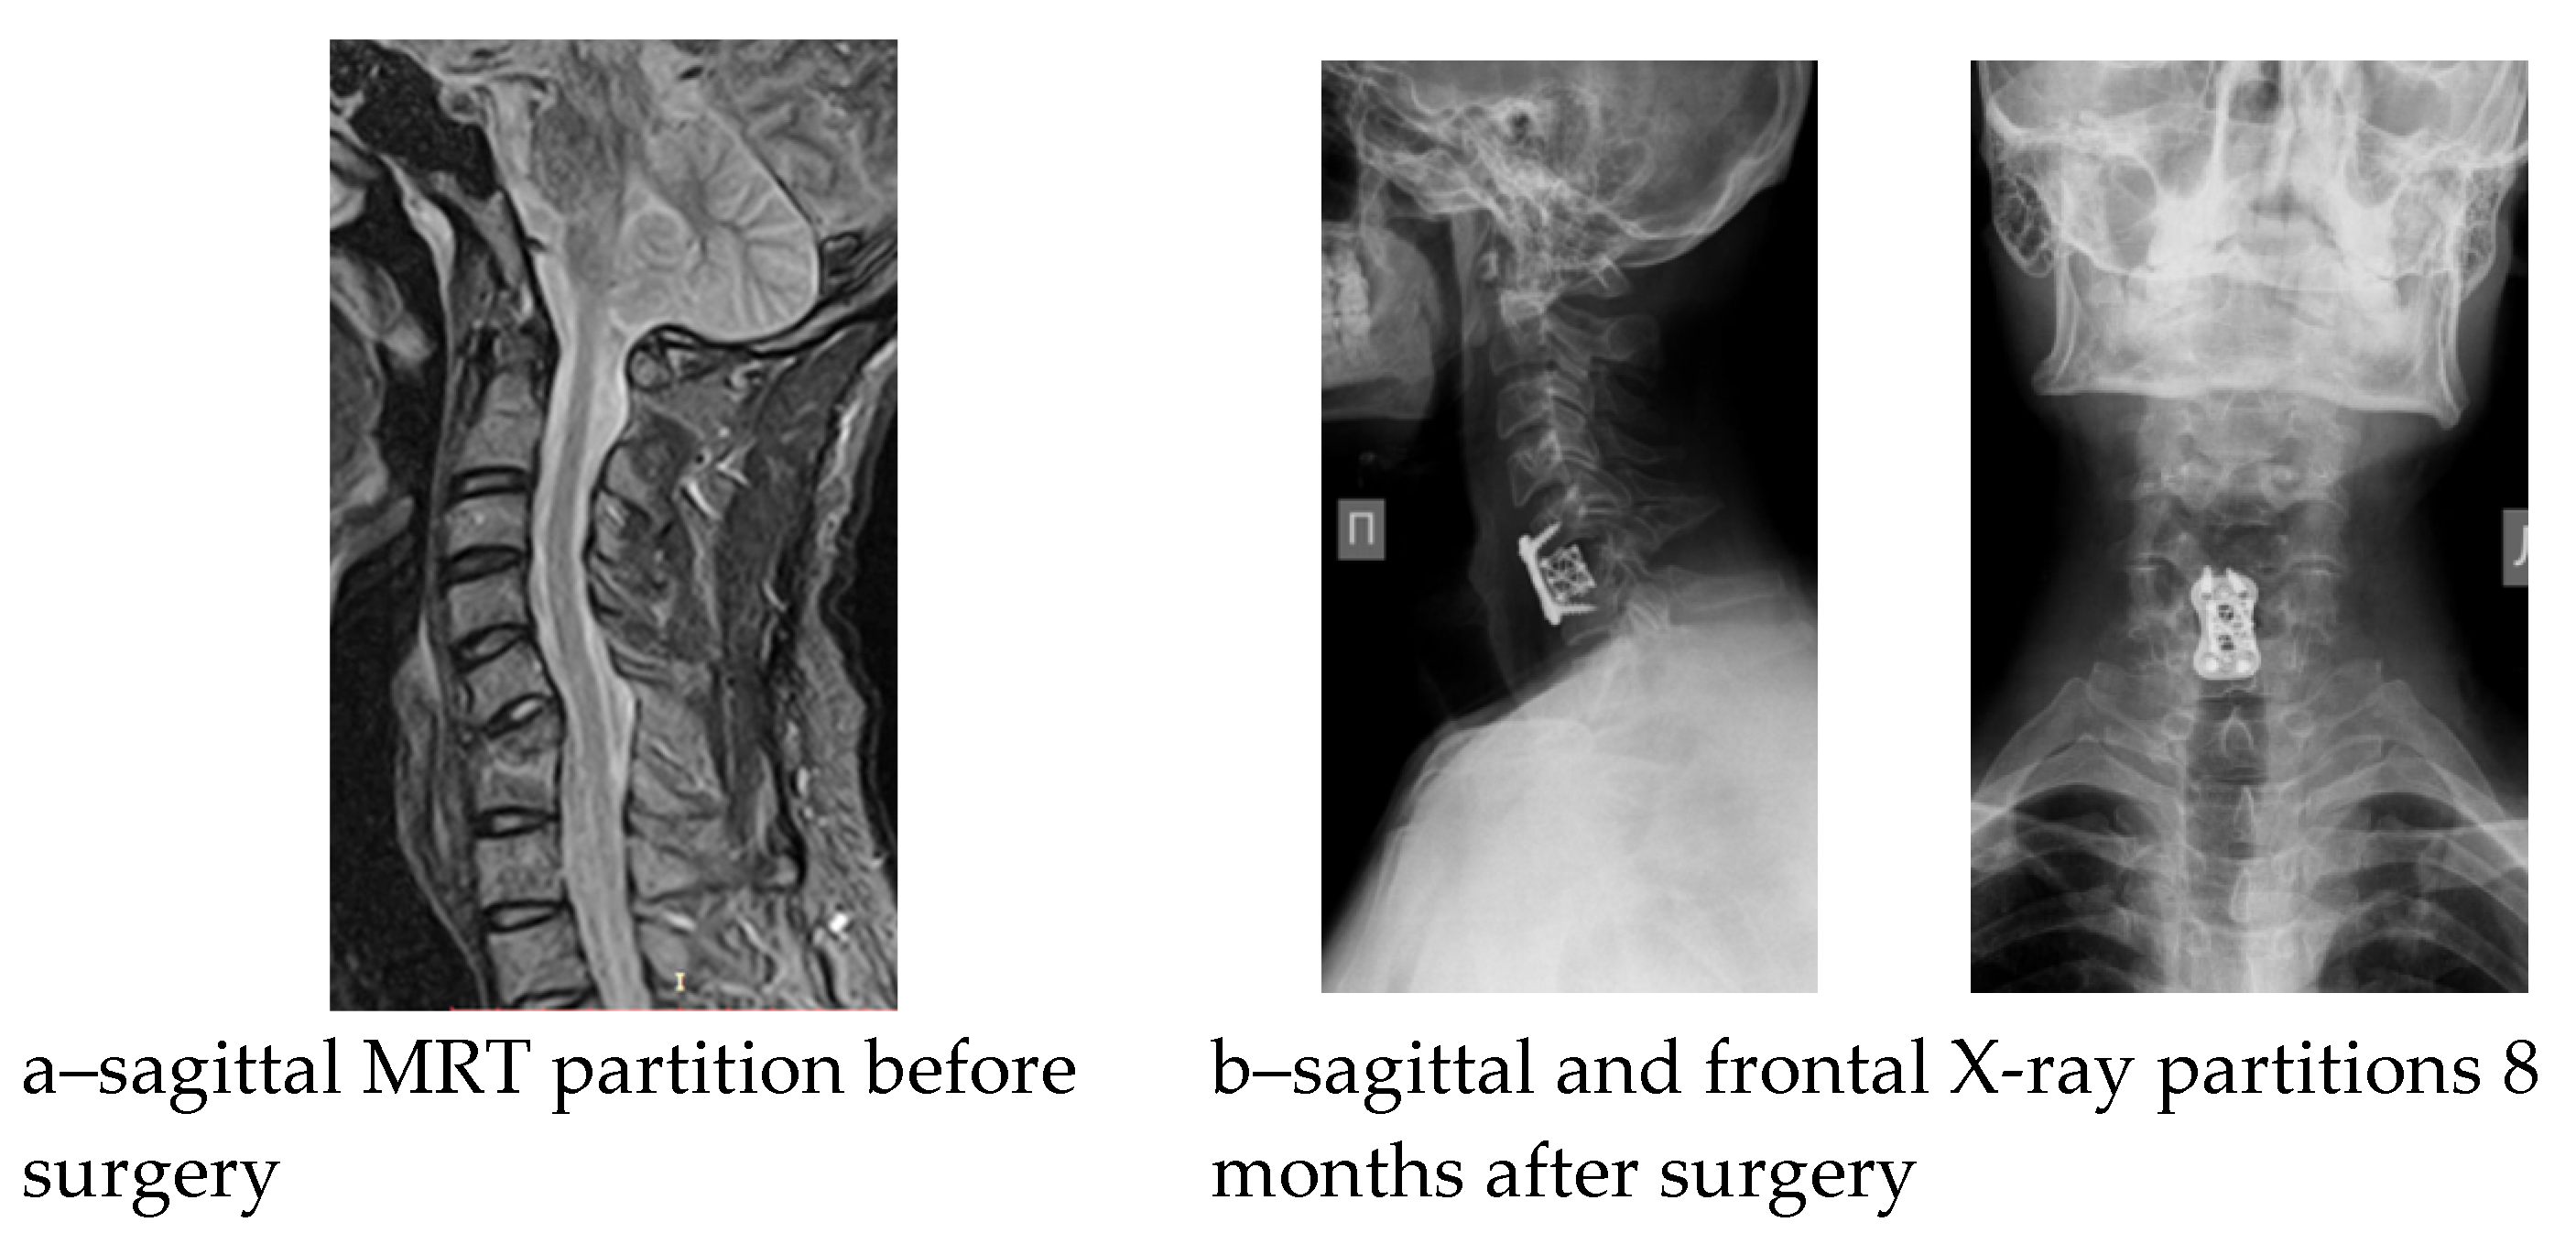

Seven postoperative complications were noted in the cohort with a predominance in the AACF + AP group; however, the reconstruction variant was not proven to have a significant impact (x2 = 3.689, p = 0.297). In the early postoperative period, three patients had a pain syndrome of 5 to 6 VAS scores in the area of the autograft (rib autograft fragment), which was controlled by a course of non-steroidal anti-inflammatory drugs in combination with physiotherapeutic treatment. In one case, 3 months after the operation, the epidural abscess persisted: C4-5 hemilaminectomy, sanitation, and posterior instrumental fixation were performed. In three cases, instability of the spinal reconstruction zone was detected, manifested by the recurrence of vertebrogenic pain syndrome; in one case, it was detected against the backdrop of deep infection of the surgical intervention zone. The development period of the aforementioned complications was 6–8 months. Revision surgeries were performed within the scope of anterior respondylodesis with a titanium mesh cage with auto bone (n1 = 2) and anterior column debridement combined with posterior screw fixation (n2 = 1). Analysis of sagittal balance showed a significant change primarily in the T1S and NTA parameters, but no significant association of these changes with the etiology of spondylitis (Table 3). The results of the surgical treatment of suboccipital and subaxial chronic spondylitis are shown in Figure 2 and Figure 3.

Figure 3.

Pre- and postoperative radiological findings of a patient with C6-7 spondylitis.